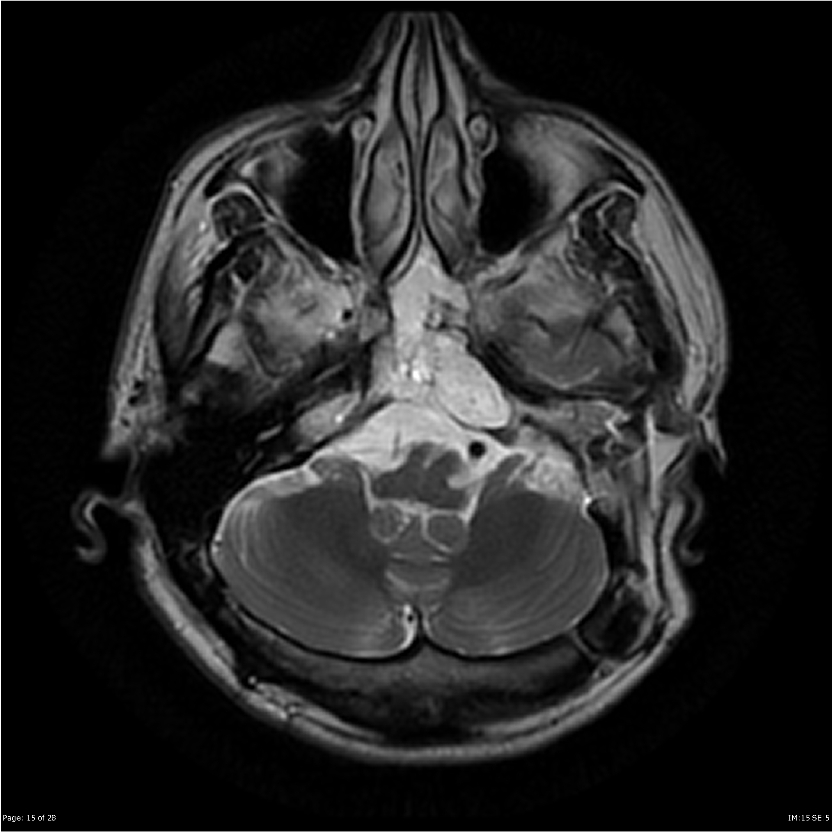

Для подтверждения наличия хордомы прибегают к таким методам диагностики, как рентген, КТ и МРТ.

Для установления точных размеров и локализации опухоли применяют КТ и МРТ. КТ представляет собой рентгенологическое исследование в разных проекциях с совместным сканированием. В результате данного исследования можно получить двух- или трехмерное изображение. Оно дает возможность определить плотность образования и выявить возможное наличие метастазов.

Процедура МРТ, в основе которой лежит применение ядерно-магнитного резонанса, больше подходит для выявления опухолей черепа. Она дает возможность изучить взаимосвязь опухоли с мозгом, кровеносными сосудами и нервами.